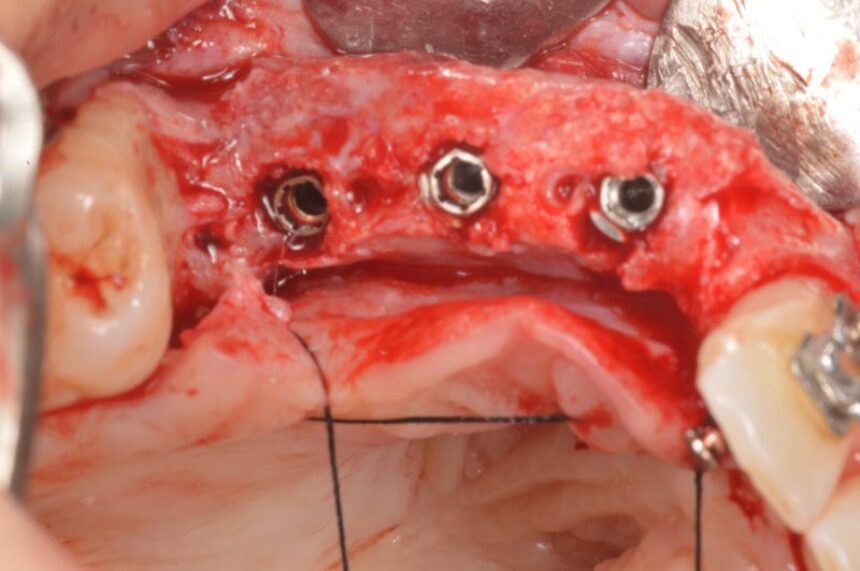

More specifically, ο Dr. Massimo Simion is one of the pioneers of the Guided Bone Regeneration procedure in the area of implant dentistry. Through his thirty-year experience, he will convey his experiences in this area, as well as the secrets of success in cases of extended deficit of the alveolar crest, in both the maxilla and the mandible, and he is going to present the management of various complications that may arise in handling such cases, which is a challenge for clinicians.

Horizontal and Vertical Ridge Augmentation: scientific background - surgical techniques – resorbable and non-resorbable membranes - bone graft harvesting from intra-oral sites – video

Surgical techniques for hard and soft tissue augmentation.